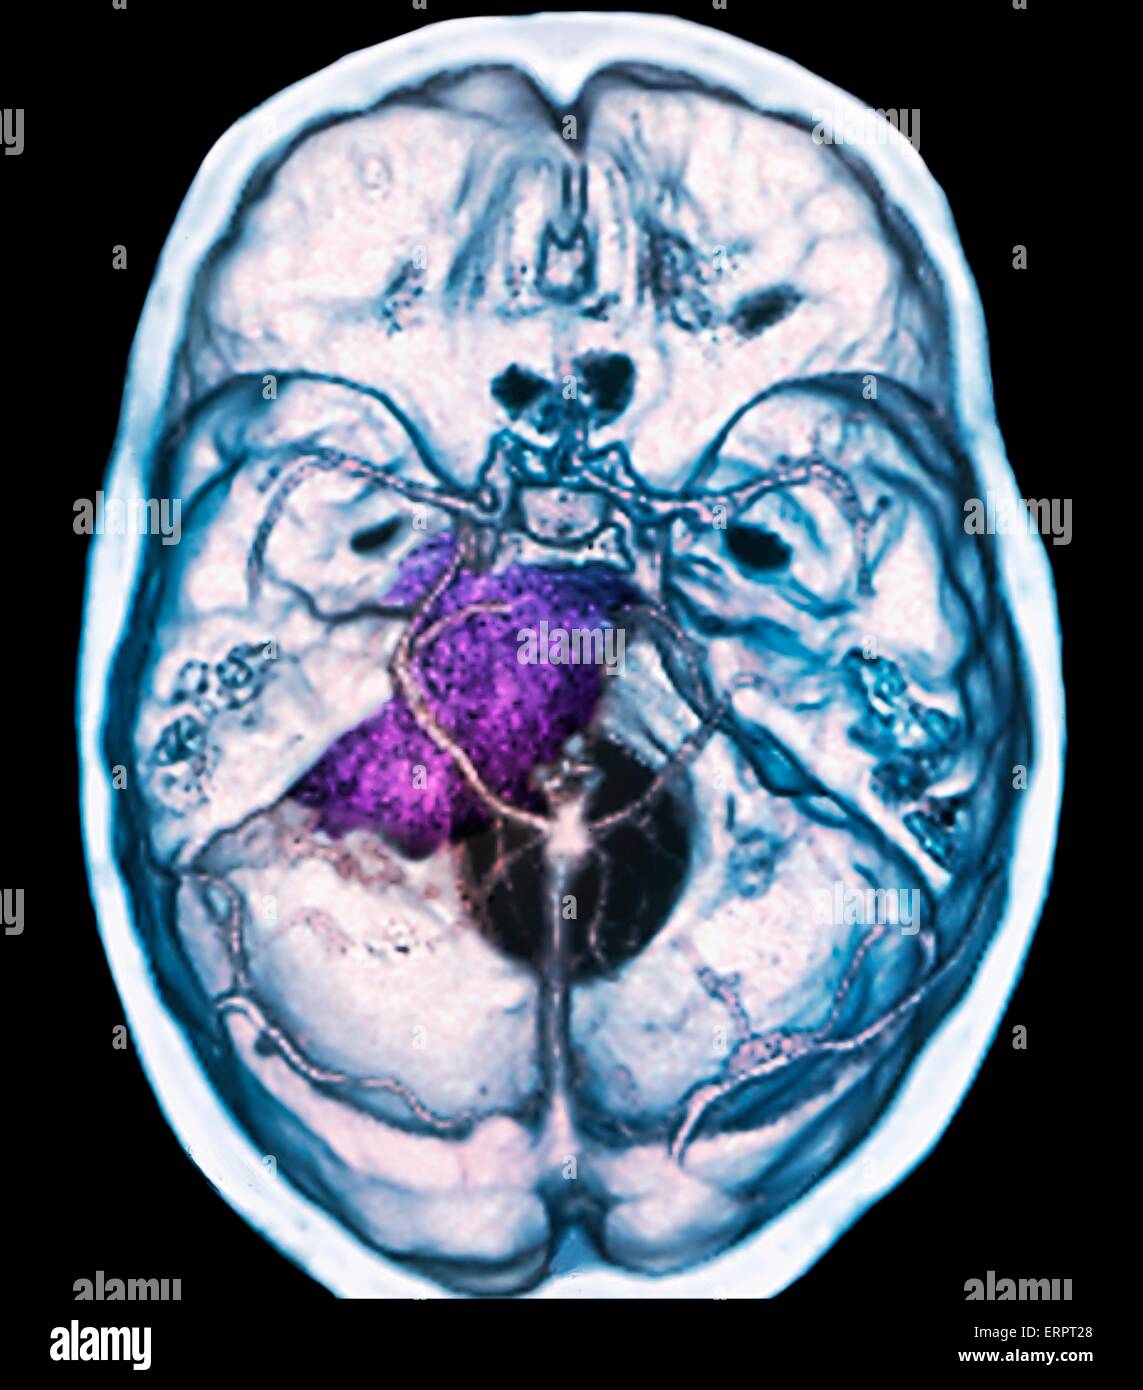

Tumeur bénigne au cerveau. La tomodensitométrie (CT de couleur) du cerveau d'un patient de 48 ans avec un méningiome (violet). Il s'agit d'une bénigne (non cancéreuse) tumeur qui découle de la méninges, les membranes qui entourent le cerveau. Banque D'Imageshttps://www.alamyimages.fr/image-license-details/?v=1https://www.alamyimages.fr/photo-image-tumeur-benigne-au-cerveau-la-tomodensitometrie-ct-de-couleur-du-cerveau-d-un-patient-de-48-ans-avec-un-meningiome-violet-il-s-agit-d-une-benigne-non-cancereuse-tumeur-qui-decoule-de-la-meninges-les-membranes-qui-entourent-le-cerveau-83480385.html

Tumeur bénigne au cerveau. La tomodensitométrie (CT de couleur) du cerveau d'un patient de 48 ans avec un méningiome (violet). Il s'agit d'une bénigne (non cancéreuse) tumeur qui découle de la méninges, les membranes qui entourent le cerveau. Banque D'Imageshttps://www.alamyimages.fr/image-license-details/?v=1https://www.alamyimages.fr/photo-image-tumeur-benigne-au-cerveau-la-tomodensitometrie-ct-de-couleur-du-cerveau-d-un-patient-de-48-ans-avec-un-meningiome-violet-il-s-agit-d-une-benigne-non-cancereuse-tumeur-qui-decoule-de-la-meninges-les-membranes-qui-entourent-le-cerveau-83480385.htmlRFERPT29–Tumeur bénigne au cerveau. La tomodensitométrie (CT de couleur) du cerveau d'un patient de 48 ans avec un méningiome (violet). Il s'agit d'une bénigne (non cancéreuse) tumeur qui découle de la méninges, les membranes qui entourent le cerveau.

Tumeur bénigne au cerveau. La tomodensitométrie (CT de couleur) du cerveau d'un patient de 48 ans avec un méningiome (violet). Il s'agit d'une bénigne (non cancéreuse) tumeur qui découle de la méninges, les membranes qui entourent le cerveau. Banque D'Imageshttps://www.alamyimages.fr/image-license-details/?v=1https://www.alamyimages.fr/photo-image-tumeur-benigne-au-cerveau-la-tomodensitometrie-ct-de-couleur-du-cerveau-d-un-patient-de-48-ans-avec-un-meningiome-violet-il-s-agit-d-une-benigne-non-cancereuse-tumeur-qui-decoule-de-la-meninges-les-membranes-qui-entourent-le-cerveau-83480384.html

Tumeur bénigne au cerveau. La tomodensitométrie (CT de couleur) du cerveau d'un patient de 48 ans avec un méningiome (violet). Il s'agit d'une bénigne (non cancéreuse) tumeur qui découle de la méninges, les membranes qui entourent le cerveau. Banque D'Imageshttps://www.alamyimages.fr/image-license-details/?v=1https://www.alamyimages.fr/photo-image-tumeur-benigne-au-cerveau-la-tomodensitometrie-ct-de-couleur-du-cerveau-d-un-patient-de-48-ans-avec-un-meningiome-violet-il-s-agit-d-une-benigne-non-cancereuse-tumeur-qui-decoule-de-la-meninges-les-membranes-qui-entourent-le-cerveau-83480384.htmlRFERPT28–Tumeur bénigne au cerveau. La tomodensitométrie (CT de couleur) du cerveau d'un patient de 48 ans avec un méningiome (violet). Il s'agit d'une bénigne (non cancéreuse) tumeur qui découle de la méninges, les membranes qui entourent le cerveau.

Tumeur bénigne au cerveau. La tomodensitométrie (CT de couleur) du cerveau d'un patient de 25 ans avec un méningiome (violet). Il s'agit d'une bénigne (non cancéreuse) tumeur qui découle de la méninges, les membranes qui entourent le cerveau. Il a été causé par ra Banque D'Imageshttps://www.alamyimages.fr/image-license-details/?v=1https://www.alamyimages.fr/photo-image-tumeur-benigne-au-cerveau-la-tomodensitometrie-ct-de-couleur-du-cerveau-d-un-patient-de-25-ans-avec-un-meningiome-violet-il-s-agit-d-une-benigne-non-cancereuse-tumeur-qui-decoule-de-la-meninges-les-membranes-qui-entourent-le-cerveau-il-a-ete-cause-par-ra-83480375.html

Tumeur bénigne au cerveau. La tomodensitométrie (CT de couleur) du cerveau d'un patient de 25 ans avec un méningiome (violet). Il s'agit d'une bénigne (non cancéreuse) tumeur qui découle de la méninges, les membranes qui entourent le cerveau. Il a été causé par ra Banque D'Imageshttps://www.alamyimages.fr/image-license-details/?v=1https://www.alamyimages.fr/photo-image-tumeur-benigne-au-cerveau-la-tomodensitometrie-ct-de-couleur-du-cerveau-d-un-patient-de-25-ans-avec-un-meningiome-violet-il-s-agit-d-une-benigne-non-cancereuse-tumeur-qui-decoule-de-la-meninges-les-membranes-qui-entourent-le-cerveau-il-a-ete-cause-par-ra-83480375.htmlRFERPT1Y–Tumeur bénigne au cerveau. La tomodensitométrie (CT de couleur) du cerveau d'un patient de 25 ans avec un méningiome (violet). Il s'agit d'une bénigne (non cancéreuse) tumeur qui découle de la méninges, les membranes qui entourent le cerveau. Il a été causé par ra